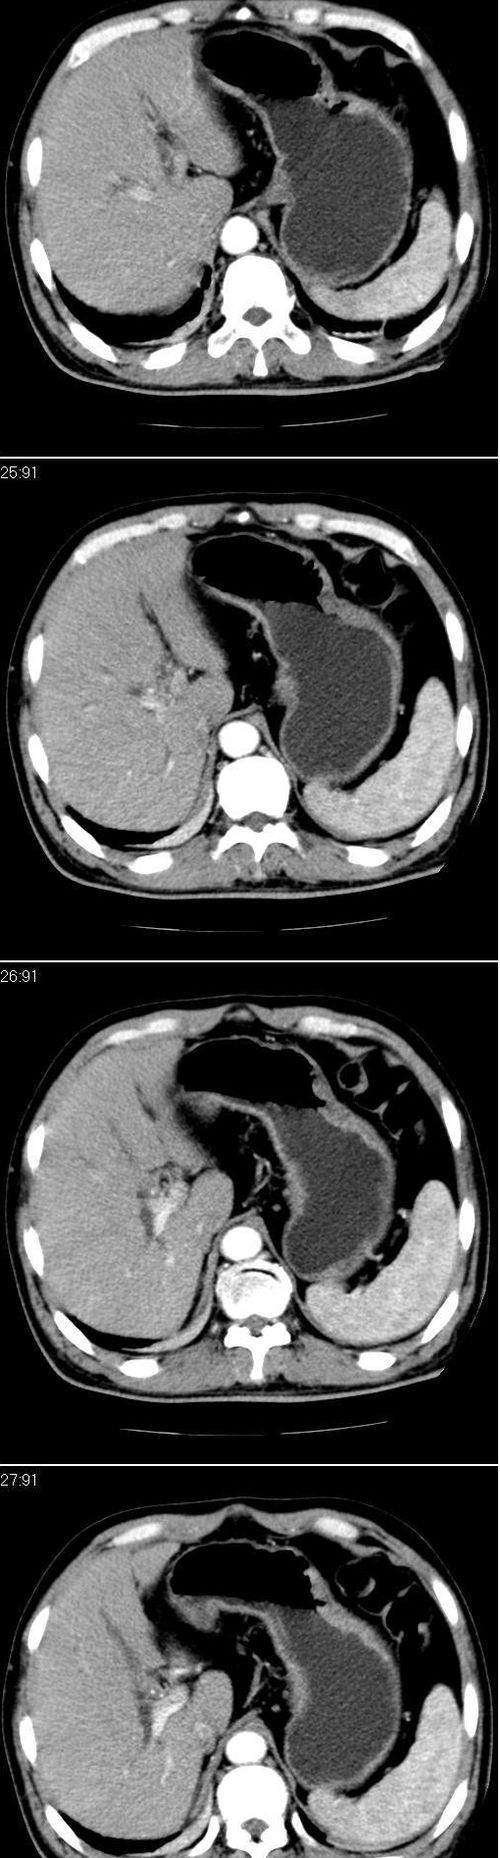

标题: CT13147:男,57岁。因胆结石阻塞性黄疸入院。 [打印本页]

标题: CT13147:男,57岁。因胆结石阻塞性黄疸入院。

男,57岁。因胆结石阻塞性黄疸入院。这是胆囊切除术后的照片,看看此片到底有什么问题。

胆总管有没有问题,尤其是肝门附近的胆总管?

肝门附近的胆总管轻度扩张 请楼主复习术前片

肝内外胆管轻度扩张,胆囊窝内见引流管考虑胆囊切除术后改变.胃窦部软组织似增厚,建议胃镜检查.

在手术切除胆囊的过程中,发现肝门部胆总管恶性占位,因为家属不同意手术,没有切除,能看出来么?

肝内外胆管轻度扩张。楼主提示左右肝管合汇区域壁稍厚。胆总管末段壁似也稍厚有轻度强化。就现有资料诊断难。